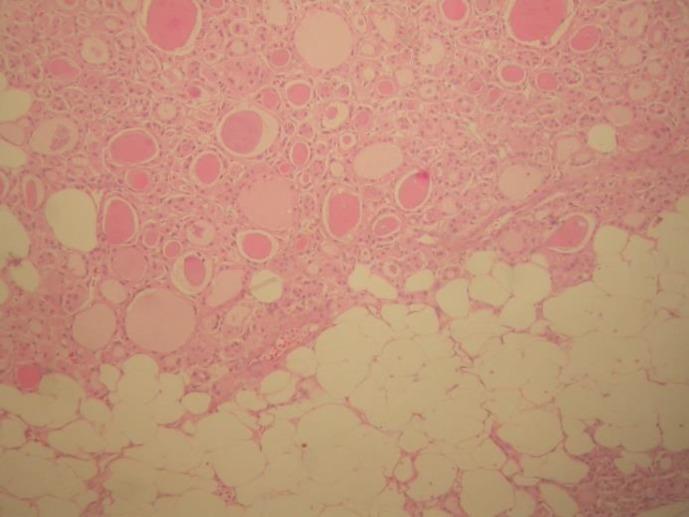

The presence of adipose tissue in the thyroid gland is a rare finding. Thyrolipoma or adenolipoma of the thyroid is a benign, encapsulated lesion of the thyroid composed of variable amounts of fat and glandular elements. This report presents a case of thyrolipoma in a 69-yr-old female presenting with neck swelling and respiratory distress. Differential diagnosis of the fat-containing thyroid lesion is also presented. Differentiation of the condition from similar lesions is necessary for accurate diagnosis of thyrolipoma

甲状腺中存在脂肪组织是一种罕见的发现。甲状腺脂肪瘤或腺脂肪瘤是一种良性的、有包膜的甲状腺病变,由不同数量的脂肪和腺性成分组成。本报告介绍了一例69岁女性甲状腺脂肪瘤病例,该患者表现为颈部肿胀和呼吸窘迫。文中还介绍了含脂肪甲状腺病变的鉴别诊断。为准确诊断甲状腺脂肪瘤,将该病症与相似病变进行区分很有必要。